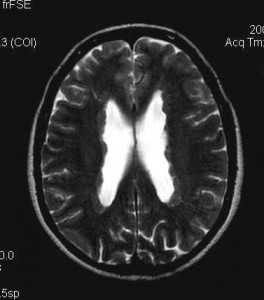

Туберозный склероз (синдром Бурневиля) встречается реже нейрофиброматоза. Его частота по данным литературы составляет около одного на 180 тыс. населения. От 20 до 40% случаев туберозного склероза унаследованы по аутосомно- доминантному типу, остальные возникли вследствии мутаций предположительно 9 и 11 пар хромосом (тип 1), либо 19 пары (тип 2). Поражение может затрагивать практически любые органы. Патогномоничными поражениями ЦНС являются корковые узлы в головном мозге и множественные субэпендимальные глиальные узлы , а также внутрижелудочковая гигантоклеточная астроцитома, встречаются сопутствующие аномалии - агенезия мозолистого тела, пахигирия, аневризмы. Характерны дерматологические проявления в виде множественных ангиофибром лица в форме «бабочки», бледные пятна на лице и груди, фибромы кожи, под ногтями и сетчатке глаза. Из других проявлений встречаются множественные ангиолипомы почек и печени, рабдомиомы сердца, лимфангиоматоз лёгких, костные склеротические и кистозные изменения. Диагноз туберозного склероза ставится при наличии у пациента 2 из перечисленных характерных признаков.

Корковые узлы - самое частое проявление туберозного склероза. Они расположены в коре головного мозга, деформируют её, захватывают прилегающее белое вещество и подвергаются кальцификации . При МРТ узлы изоинтенсивны серому веществу на Т1-взвешенных МРТ и чуть гиперинтенсивнее его на Т2-взвешенных. Контрастирование наблюдается в 5% случаев. В белом веществе обнаруживаются тяжи , отходящие радиально от желудочков. Корковые узлы и тяжи нередко называют «гамартомами», хотя они представляют собой скорее демиелинизацию и кальцификацию, чем истинную гетеротопию.

Туберозный склероз. Гамартомы. КТ, Т2-зависимая МРТ и FLAIR

Субэпендимальные, то есть проецирующиеся в желудочек, но растущие со стороны паренхимы мозга, узлы чаще расположены рядом с хвостатым ядром или гипоталамической бороздой сразу за отверстием Монро, реже в области III, IV желудочков и Сильвиева водопровода. На Т2-взвешенных томограммах субэпендимальные узлы умеренно гиперинтенсивны и часто содержат кальцинаты . От астроцитом их отличает не столь яркий сигнал и меньшие размеры. Контрастирование при введении препаратов гадолиния иногда наблюдается и в субэпендимальных узлах , и всегда в астроцитомах.

Туберозный склероз. Субэпендимальные узлы. Аксиальная Т-зависимая МРТ.